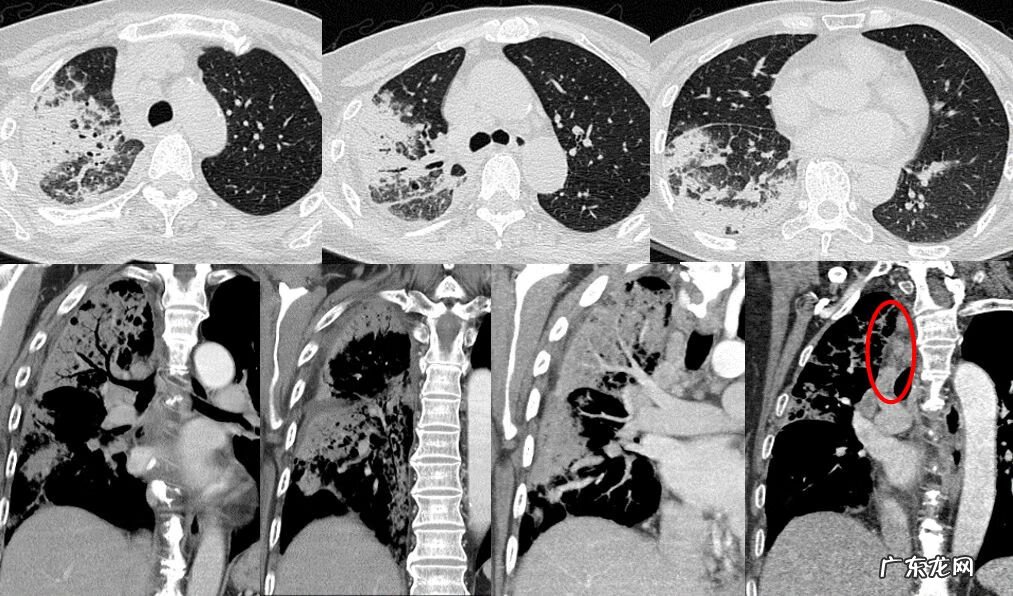

大叶性实变型也就是双下肺实变影,伴有支气管充气征 。这是一位52岁的女性,咳嗽胸闷3个月,咳白色粘痰,由于抗细菌及真菌效果不佳,当时考虑肿瘤或者OP,但是仔细看,它的叶间裂后移,肺的体积是缩小的,支气管可见不规则轻度扩张,这也提示病变是收缩的概念,并不是像肿瘤一样的膨胀性生长的改变 。肺穿刺活检证实OP,激素治疗3月,肺内病变基本吸收仅残留少许磨玻璃密度影 。

激素治疗3月后

这是一位71岁的女性,咳嗽咳痰,发热20余天,最高体温39度,抗炎效果不佳 。右肺的大片状实变影,叶间裂积液,还有淋巴结增大,增强后病灶密度不均匀,明显强化,30hu以上 。仔细观察细支气管,末梢有一种扩张、牵拉的改变,血管走行未见明显异常 。最开始诊断为大叶性肺炎,没有想到OP,因为影像学表现很相似,有实变磨玻璃影、小叶间隔增厚,胸腔 积液等改变,患者临床表现也类似感染,经肺穿刺活检证实为OP 。激素治疗2年,肺内病变基本吸收仅残留少许磨玻璃密度影,但是左肺又新出现磨玻璃密度影,这就是病情反复的特点 。

激素治疗2年